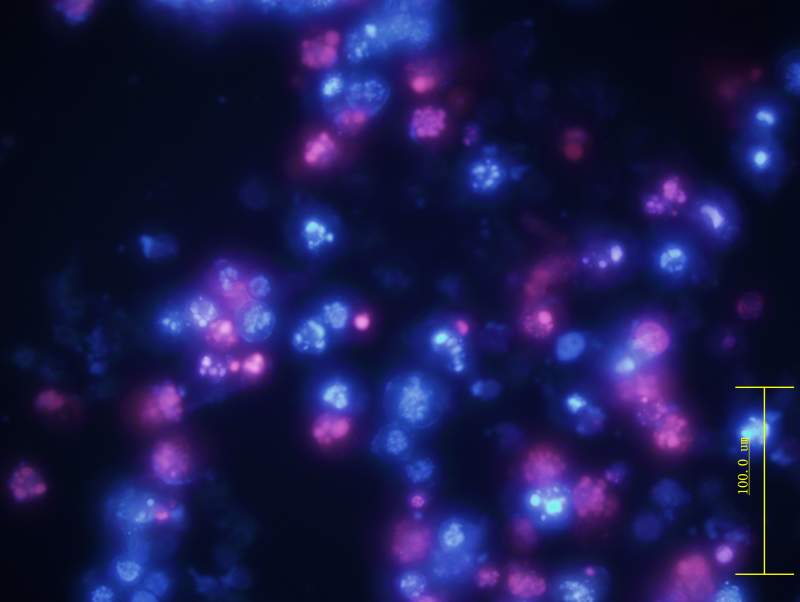

ϸ°û¾­¹ýÎïÀí½áºÏ»¯Ñ§ÁÆ·¨36 Сʱºó£¬ ÓÃhoechst Ⱦɫ ºÍPIȾɫ£¬¹Û²ìÆÚÐÎ̬¡£

45-3.jpg

Õû¸öϸ°ûµ­À¶É«£¿ÊǺËËéÁÑ¡¢ºËÈܽ⻹ÊÇhoechest ´ãÃð£¨Ï¸°ûͬʱHoechst ºÍPIȾɫ£©

45M-2.jpg

ºìɫΪ»µËÀÂð£¿Õû¸öϸ°ûµ­À¶É«ÎªÊǺËËéÁÑ¡¢ºËÈܽ⻹ÊÇhoechest ´ãÃð£¨Ï¸°ûͬʱHoechst ºÍPIȾɫ£©